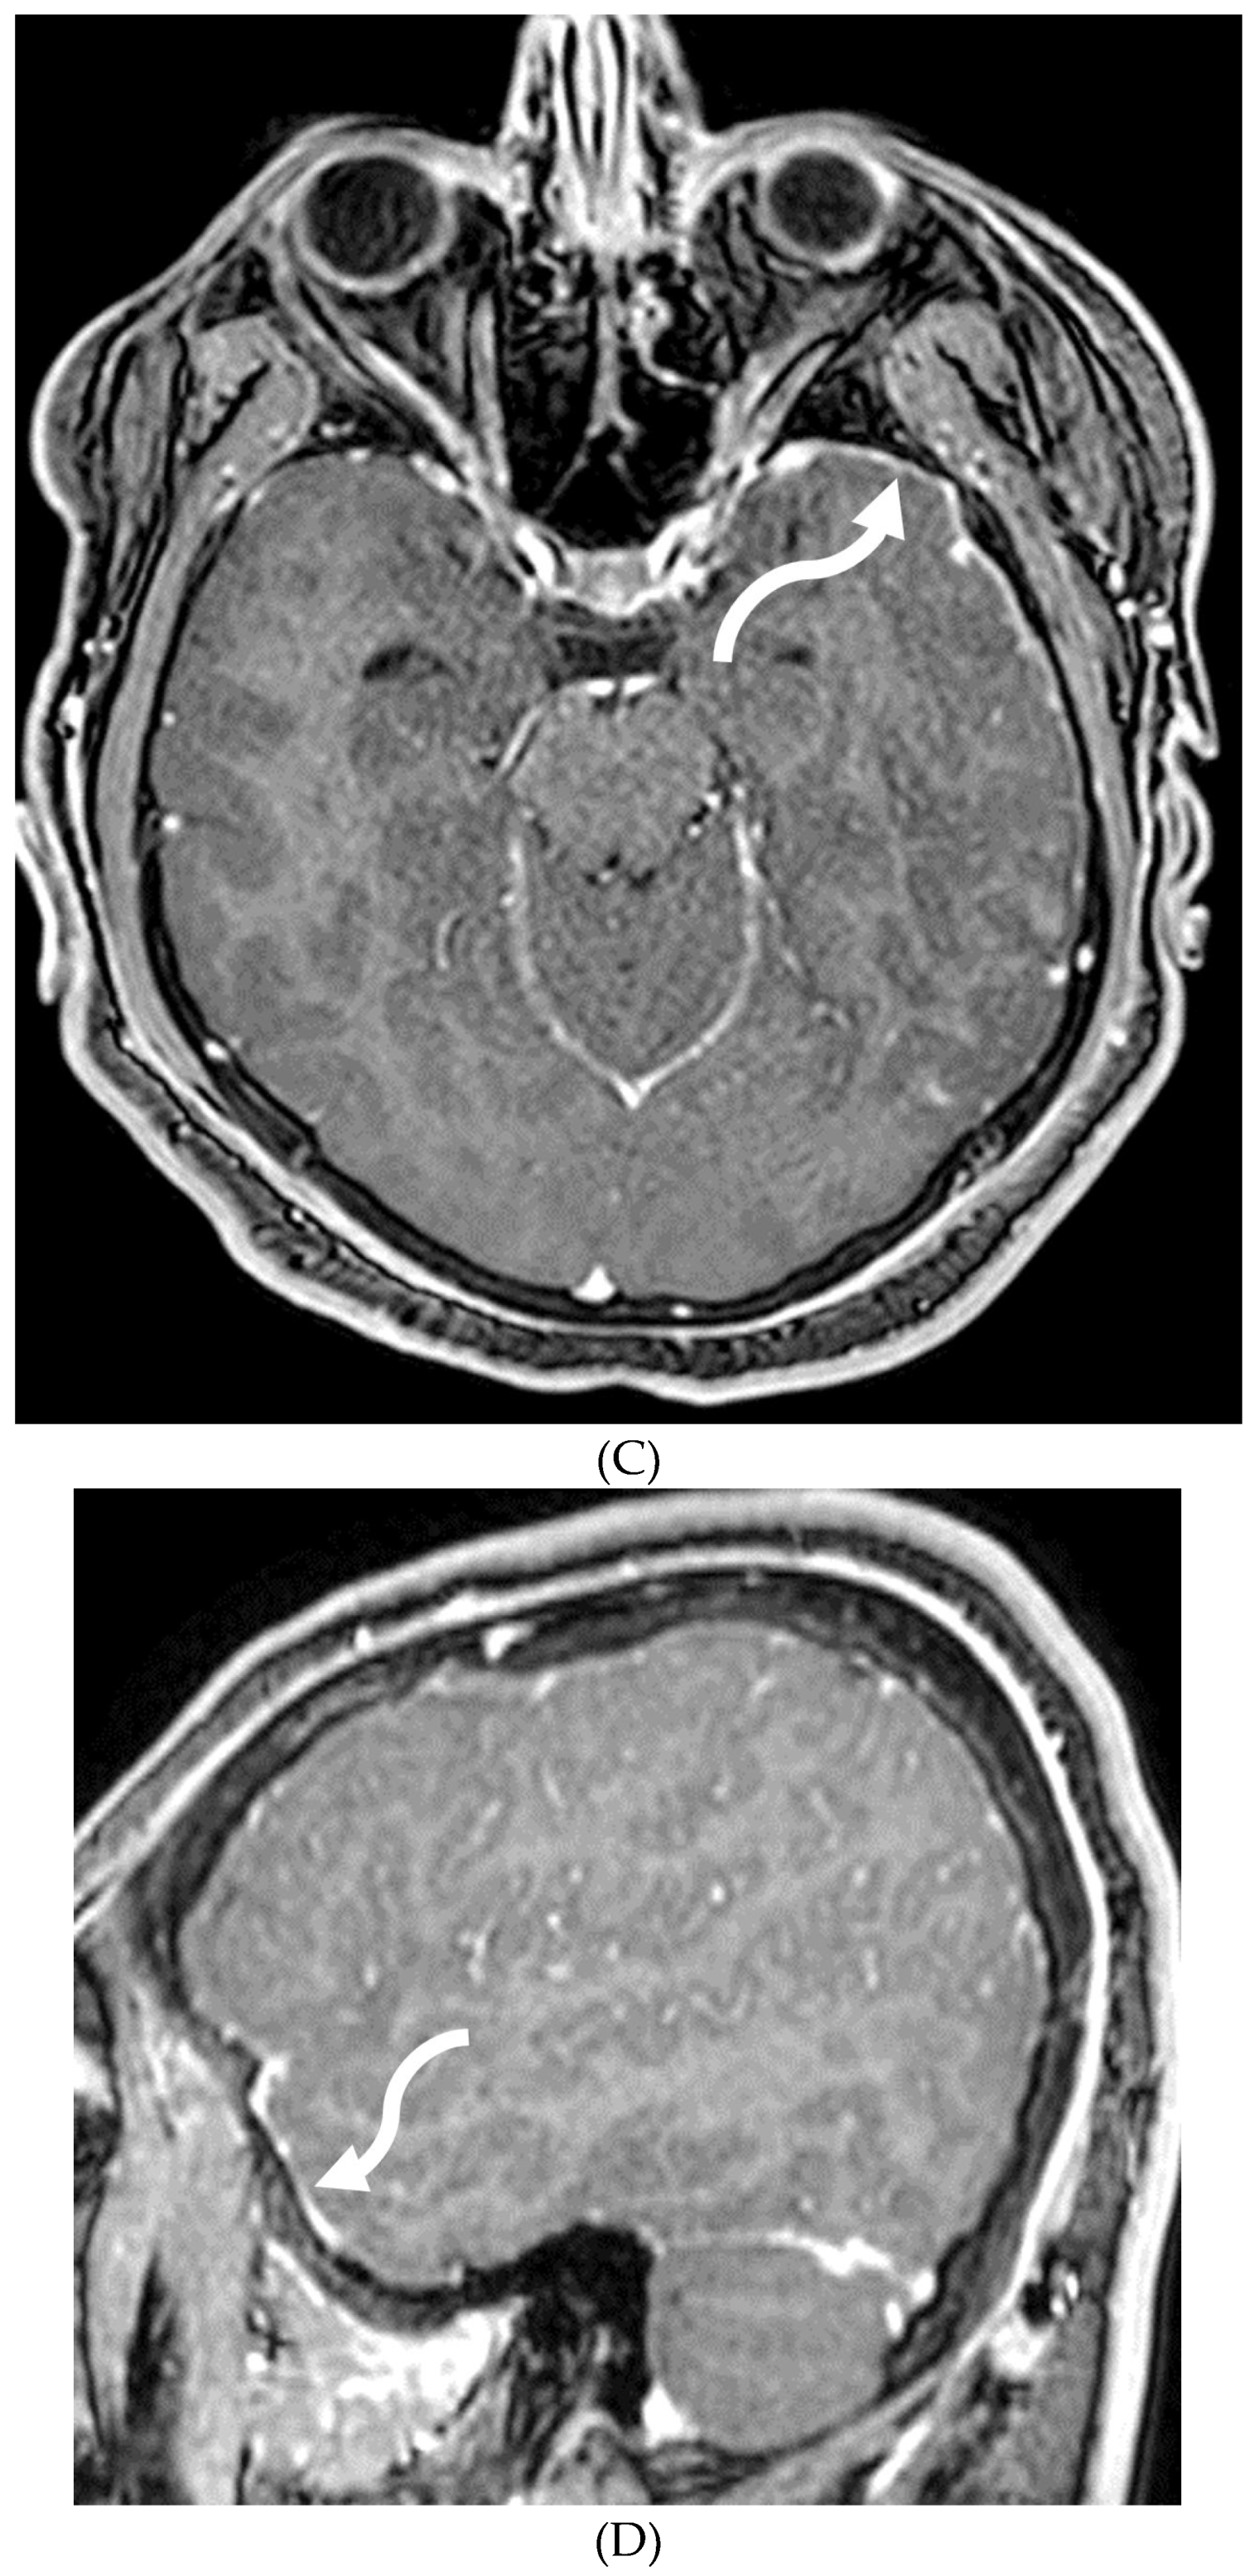

- Agarwal A, Kapur G, Altinok D. Childhood posterior reversible encephalopathy syndrome: Magnetic resonance imaging findings with emphasis on increased leptomeningeal FLAIR signal. Neuroradiol J. 2015 Dec;28(6):638-43. Epub 2015 Oct 29. PMID: 26515749; PMCID: PMC4757130. [CrossRef]

- Ishikura K, Ikeda M, Hamasaki Y, Hataya H, Shishido S, Asanuma H, Nishimura G, Hiramoto R, Honda M. Posterior reversible encephalopathy syndrome in children: its high prevalence and more extensive imaging findings. Am J Kidney Dis. 2006 Aug;48(2):231-8. PMID: 16860188. [CrossRef]

- Bartynski WS. Posterior reversible encephalopathy syndrome, part 1: fundamental imaging and clinical features. AJNR Am J Neuroradiol. 2008 Jun;29(6):1036-42. Epub 2008 Mar 20. PMID: 18356474; PMCID: PMC8118828. [CrossRef]

- Hamilton BE, Nesbit GM. Delayed CSF enhancement in posterior reversible encephalopathy syndrome. AJNR Am J Neuroradiol. 2008 Mar;29(3):456-7. Epub 2008 Jan 9. PMID: 18184835; PMCID: PMC8118892. [CrossRef]